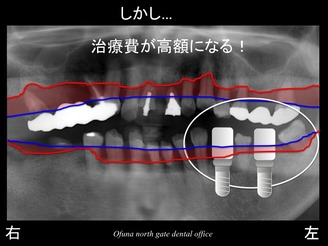

しかし、インプラント治療の場合、費用の問題がどうしてもあります。

今回、右側 や 上顎前歯部 にもインプラント治療を予定しています。

さらに下顎左側までインプラント治療となると これは大変です。

今回の治療で最優先となる治療は、右側です。